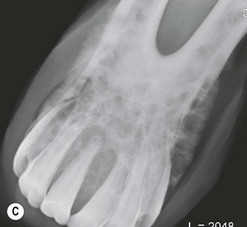

The condition is usually presented as a painful, hot, progressive swelling of the mandible with a characteristic ‘sun-burst’ radiographic appearance of bone lysis and irregular deposition of trabecular reactive new bone44 (Fig. 11.12). Pathological fractures can occur in affected bones.

image image image image image

Fig. 11.12 (A) & (B) This 5-year-old Irish Draught mare was presented with a 4-week history of a mandibular swelling, gingival bleeding, weight loss and dysmasesis. The mandibular incisors were palpably loose and the mandible was warm to the touch and mildly painful on palpation. (C) & (D) Lateral and occlusive radiographs gave the suspicion of a neoplastic lesion. (E) A bone biopsy was taken from several sites, and the horse was diagnosed with osteosarcoma.

Diagnostic confirmation

Their radiographic appearance is highly suggestive, but biopsy provides the only definitive diagnosis. There is a characteristic combination of cortical bone destruction and periosteal new bone formation giving the area a ‘sunburst’ radiographic appearance.

Bone biopsies of osteosarcoma are sometimes easy to obtain, since the bone is usually softer than normal and the medullary cavity is filled with diagnostically significant friable pink to white material containing variable amounts of cancellous bone (Fig. 11.12E). It is easy to miss tumor tissue in small bone biopsies, and florid, non-neoplastic reactive bone or fracture callus can easily be mistaken histologically for neoplasia. Multiple biopsies should, therefore, be collected from sites identified by radiography or CT or MR imaging methods, but this is not an easy procedure.